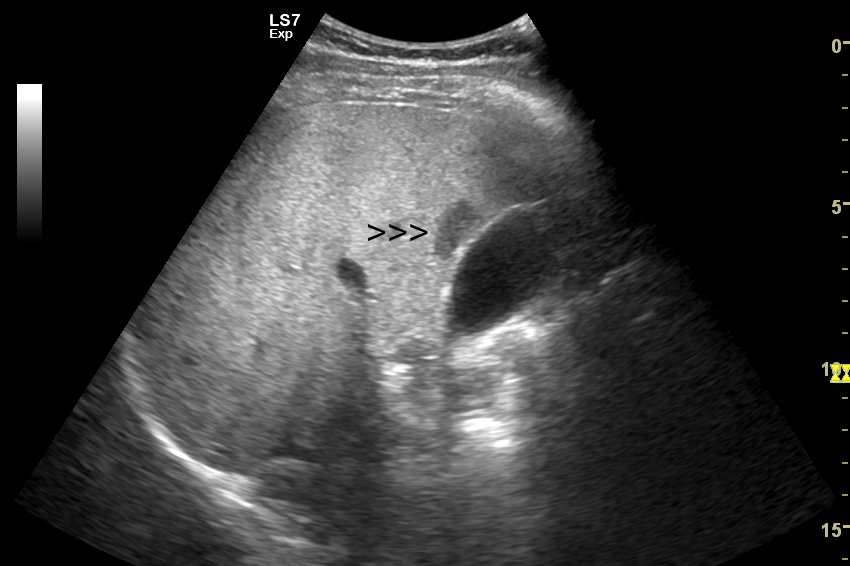

W badaniu USG w prezentacji B w niestłuszczonej wątrobie typowy naczyniak włośniczkowy lokalizuje się w pobliżu gałęzi żyły wątrobowej, a prezentuje się jako ostrookonturowana, hyperechogenna, jednorodna, krągła lub owalna zmiana ogniskowa. Ze względu na niską prędkość przepływu krwi i wynikające z tego ograniczenie detekcji w trybie color-Doppler w naczyniaku nie rejestruje się sygnału. Z kolei w trybie mikrounaczynienia (MVI / MVF) w zależności od czułości aparatury w naczyniaku można zaobserwować delikatny sygnał w postaci „poprószonego śniegu”.

W przypadku zarejestrowania w obrębie hyperechogennej zmiany ogniskowej wątroby w trybie kolorowego Dopplera lub Dopplera mocy (ang. power Doppler) drobnego naczynia lub naczyń, w szczególności krętych i o nieregularnym przebiegu, należy brać pod uwagę prawdopodobieństwo obecności złośliwej zmiany metastatycznej lub innego rodzaju zmiany ogniskowej.